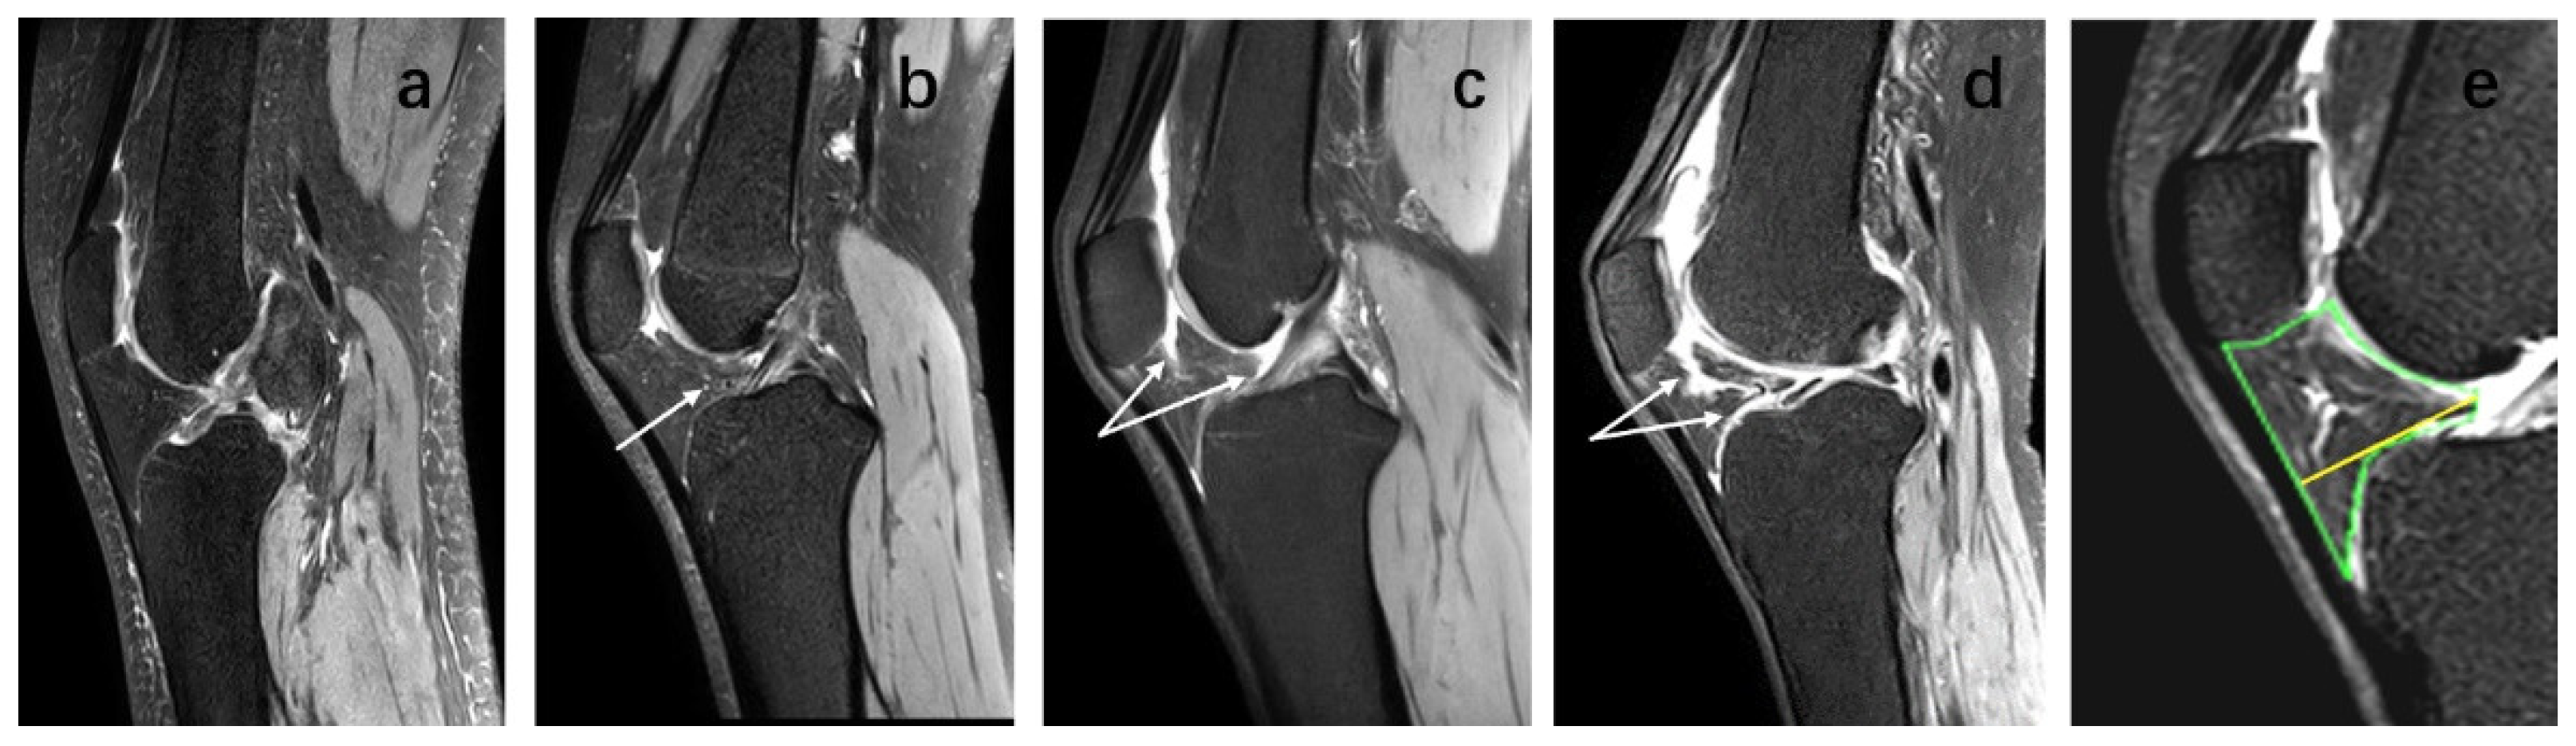

On sagittal T2-weighted MR Images, the IPFP boundary was manually delineated to measure the IPFP, and the maximum cross-sectional area (CSA) was calculated. The maximum sagittal thickness of the IPFP was measured manually, and a line perpendicular to the patellar tendon was drawn from the anterior to posterior surface, and this was used to indicate the IPFP depth. IPFP signal intensity alteration on MRI were assessed by an experienced orthopedic surgeon and an experienced radiologist using T2-weighted MRI. The sagittal plane with the most significant increase in IPFP signal was selected as the plane of interest for study, and edema was defined as high signal on the fat-suppression sequence. The sagittal plane of the IPFP was segmented using MIMICS, and the area indicated by the white arrow within the IPFP represented the high signal regions [25] (Figure 3). IPFP signal intensity alteration was graded as follows: Grade 0 = none; Grade 1 ≤ 10% of the area; Grade 2 = 10–20% of the area; Grade 3 ≥ 20% of the area [18]. Two observers observed alone, and a random cross-check was performed with the other observer. The intra-class correlation coefficient (ICC) was 0.94 for intra-observer reliability, and inter-observer reliability was 0.93.

Figure 3.

IPFP signal intensity alteration, IPFP maximum cross-sectional area (CSA) and IPFP depth on sagittal planes of T2-weighted images. IPFP signal intensity alteration graded as follows: (a) Grade 0 = none; (b) Grade 1 ≤ 10% of the area; (c) Grade 2 = 10–20% of the area; (d) Grade 3 ≥ 20% of the area. The area indicated by the white arrow within the IPFP represent the high signal regions. (e) The green area indicates the IPFP maximum CSA. The yellow line which perpendicular to the patellar tendon was drawn from the anterior to posterior surface indicates IPFP depth.